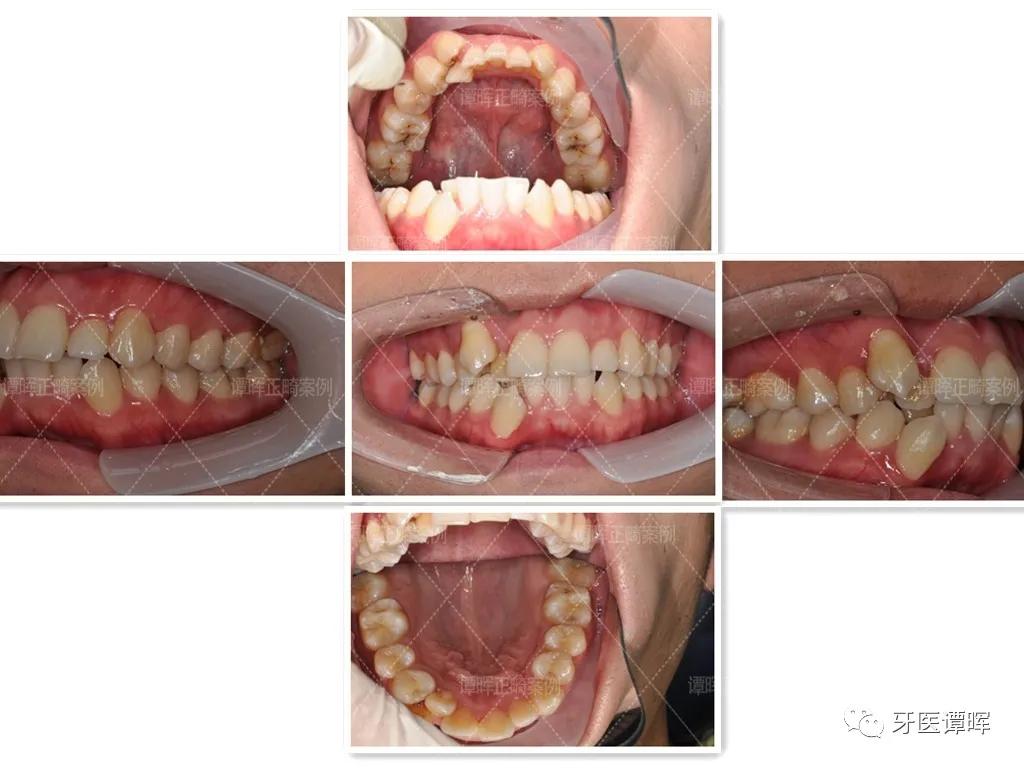

矫正前

矫正之前因牙齿拥挤使嘴巴看起来有点突,下门牙畸形错颌,没有办法正常咬食物,也因虎牙与另一颗牙重叠,吃东西时特别容易塞牙,因此牙周也不是很好。